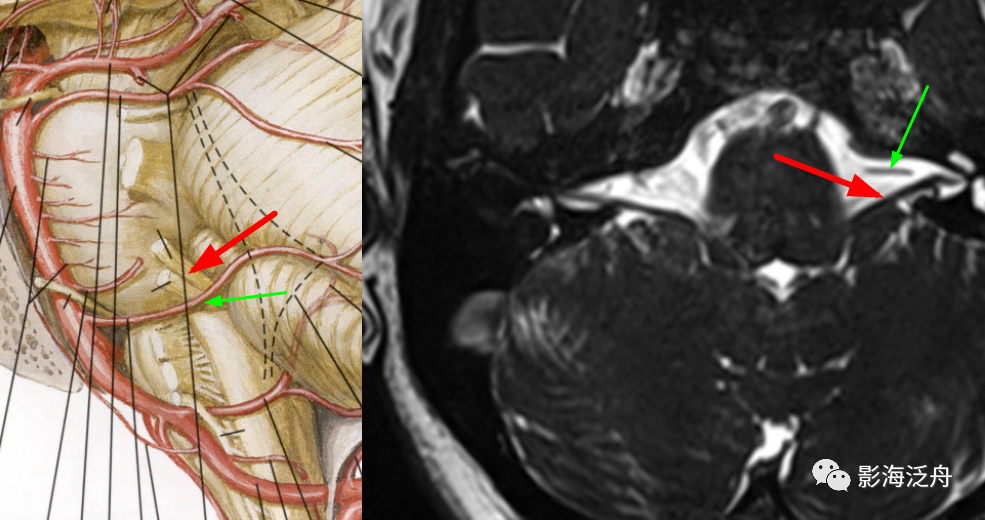

在MRA图上观察一下这三支动脉。如图所示,红箭:小脑上动脉;绿箭:右侧小脑下前动脉;小脑下后动脉未在图中显示(MRA中小脑下后动脉很少能显示出来)。

在轴位MR图像上观察并准确辨识出相应的神经和血管,常规的FSE T2WI也可以看到这些颅神经和血管,但不够清晰,尽量还是在更专业的3D重T2WI序列或3D B_FFE序列上观察,如下图↓